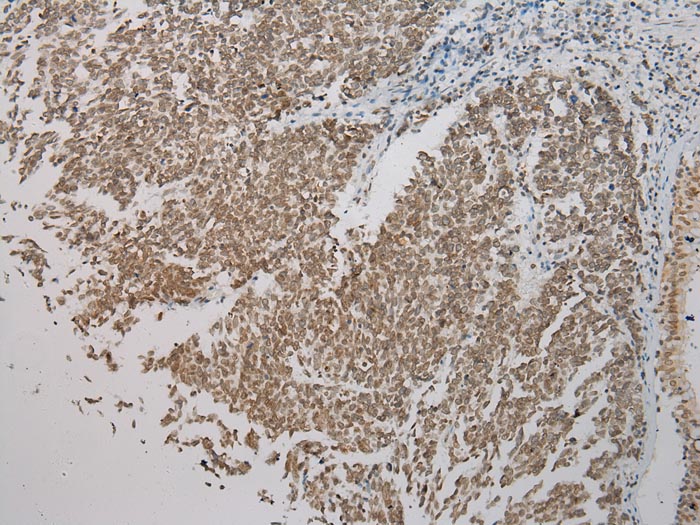

Immunohistochemical analysis of paraffin-embedded Human Lung cancer tissue using #43434 at dilution 1/200.